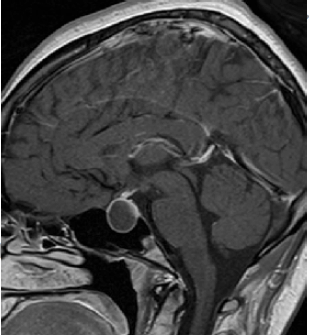

Uma paciente de 30 anos de idade, apresentando fadiga, sonolência e intolerância ao frio, chegou ao pronto-socorro. Foram solicitados exames laboratoriais (que evidenciaram (VR = 0,45 a 4,5 mUI/L) TSH = 1 mUI/L, T4 = 3 mg/dL (VR = 4,5 a 12,6 mg/dL) e T3 = 61 mg/dL (VR = 80 a 180 mg/dL), perfil hormonal (única alteração foi prolactina = 49 mg/mL (VR = 2,83 a 30 mg/mL) e ressonância magnética do encéfalo.

A respeito desse caso clínico e da imagem de ressonância magnética apresentada, julgue os itens a seguir.

Deve-se solicitar campimetria para avaliação de compressão do quiasma.Comentários